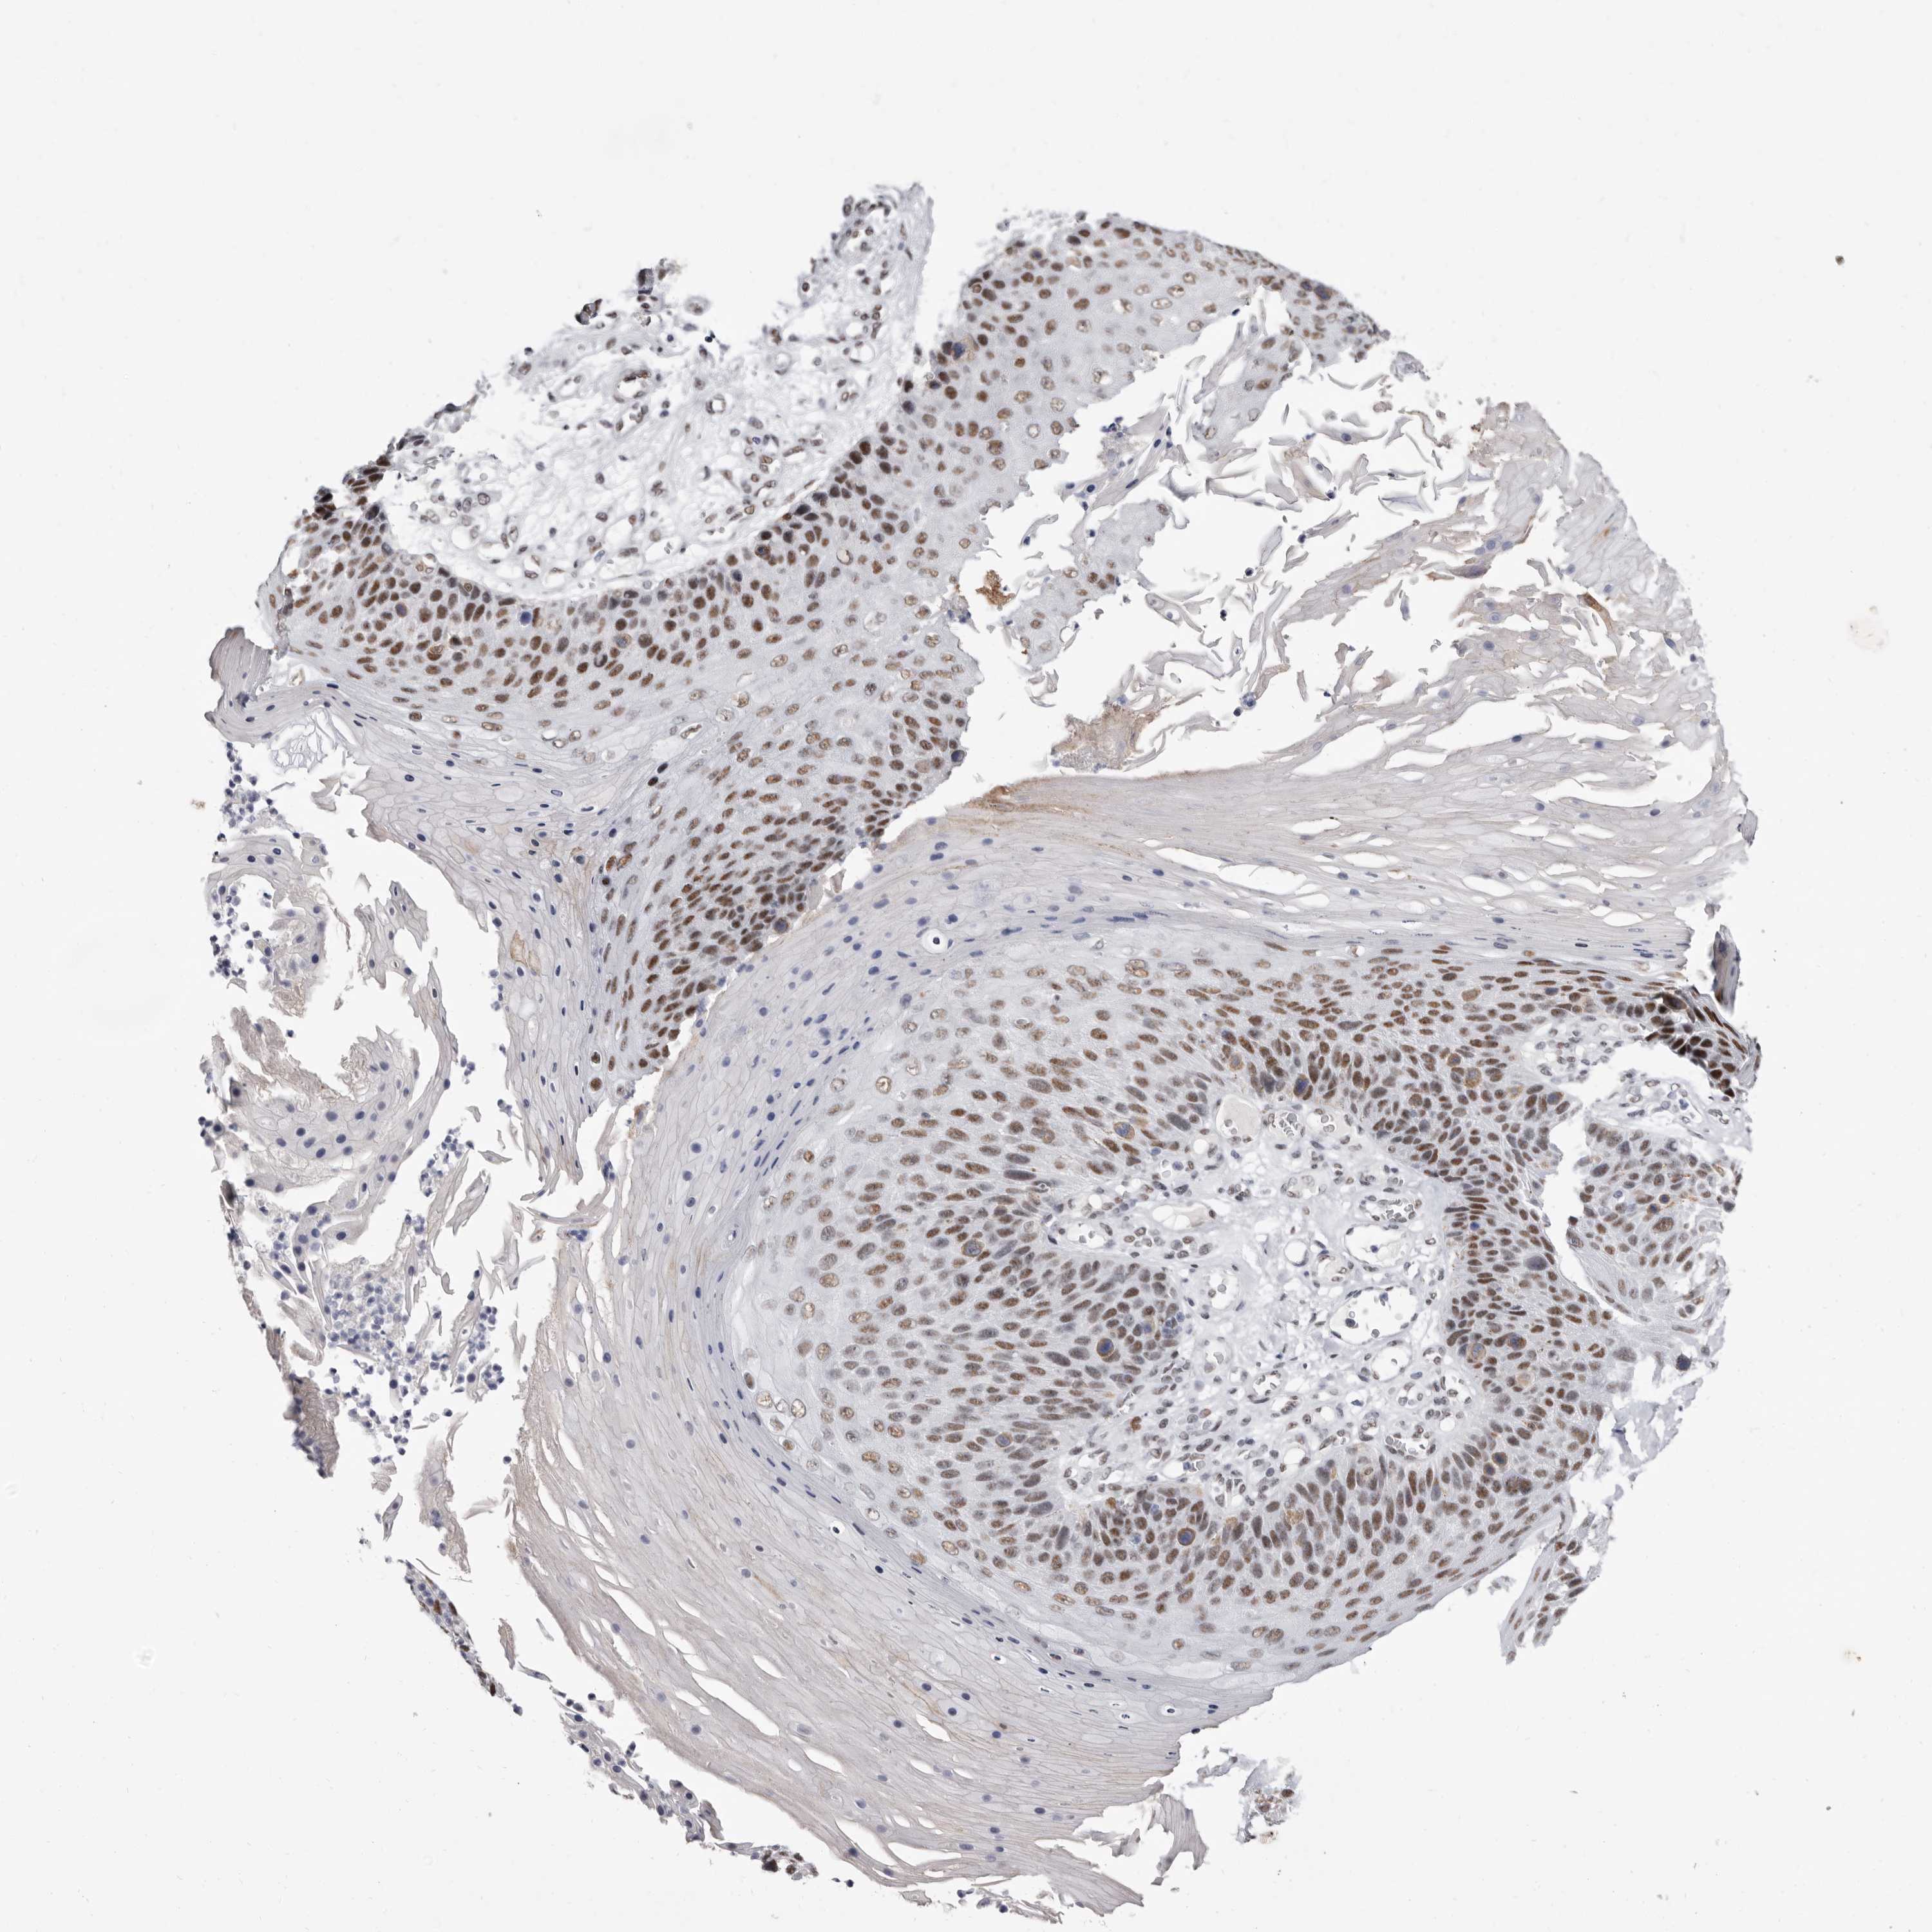

CANCER SKIN CANCER Show tissue menu

Basal cell and squamous cell cancer

SKIN CANCER - Protein expressioni

A mouse-over function shows sample information and annotation data. Click on an image to view it in a full screen mode. Samples can be filtered based on level of antibody staining by selecting one or several of the following categories: high, medium, low and not detected. The assay and annotation is described here.

Each image is clickable and will lead to virtual microscopy that enables deeper exploration of all samples and also displays staining intensity scores, fraction scores and subcellular localization as well as patient and tissue information for each sample.

Antibody HPA028461

Basal cell carcinoma

Squamous cell carcinoma, NOS

Squamous cell carcinoma, metastatic, NOS